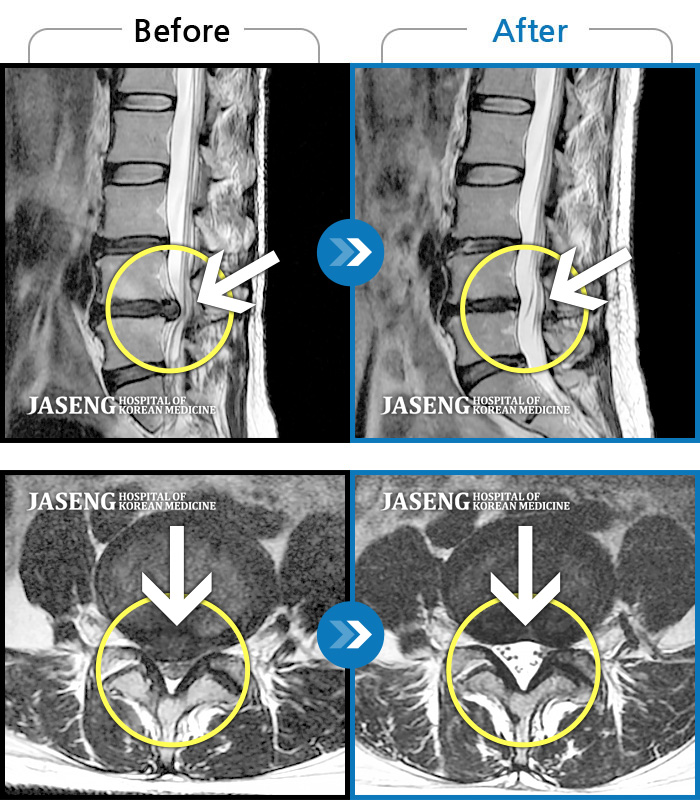

Before

After

환자에게 사전 동의를 받아 동일 조건에서 촬영되었습니다.

개인에 따라 치료 후 부작용이 발생할 수 있으니 의료진과 상담 후 치료를 진행하시기 바랍니다.

우측 허리 엉덩이부터 다리 당김, 통증

양측 허리, 우측 엉덩이에서 허벅지 뒤쪽까지 통증